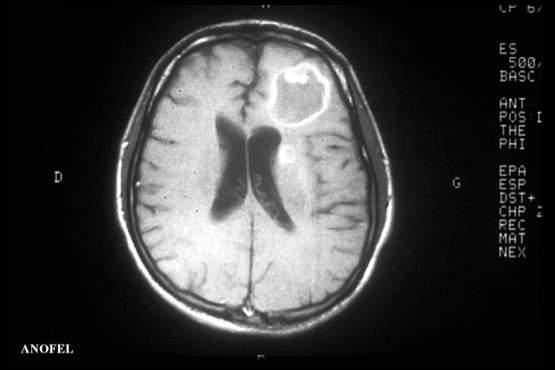

Infection cérébral

(toxoplasmose)